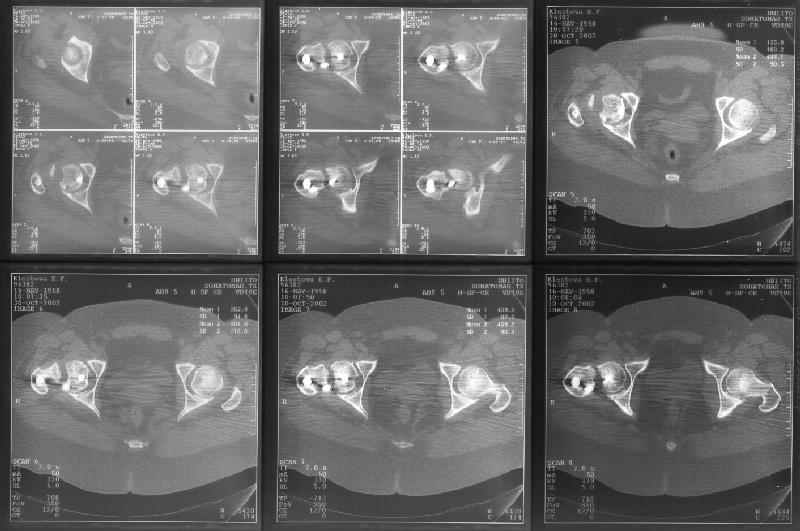

The nail has just been removed through old incisions. The neck is not healed, the shaft is partially healed (image 2).

The biggest problem here is the femoral neck nonunion in a 44 yo obese (?weight) patient. No femoral head AVN apparent on plain xray but a significant fracture gap with a verticle fracture line on AP. If you can get that to heal you will be doing her a great service. The femoral shaft is still secondary.

A valgus producing osteotomy (subtrochanteric, lateral closing wedge) combined with hip screw side plate may give the best chance of healing the femoral neck. Whether or not to open the femoral neck fracture site, bone graft it or use additional fixation are all considerations.

IMHO the problem is malreduction of the femoral neck. Using a recon nail or Miss-A-Nail for combination femoral neck and shaft fracture contributes to the problem because: